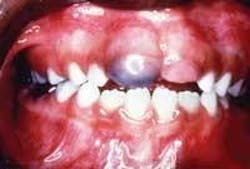

A 7-year-old male visited a pediatric dentist for a check-up. Oral examination revealed a soft, bluish swelling around the right maxillary central incisor.

No unusual or abnormal findings were identified during the extraoral examination. Intraoral examination revealed a mixed dentition. A blue swelling, which surrounded the right maxillary central incisor, was noted (see photo). The lesion was soft and fluctuant.